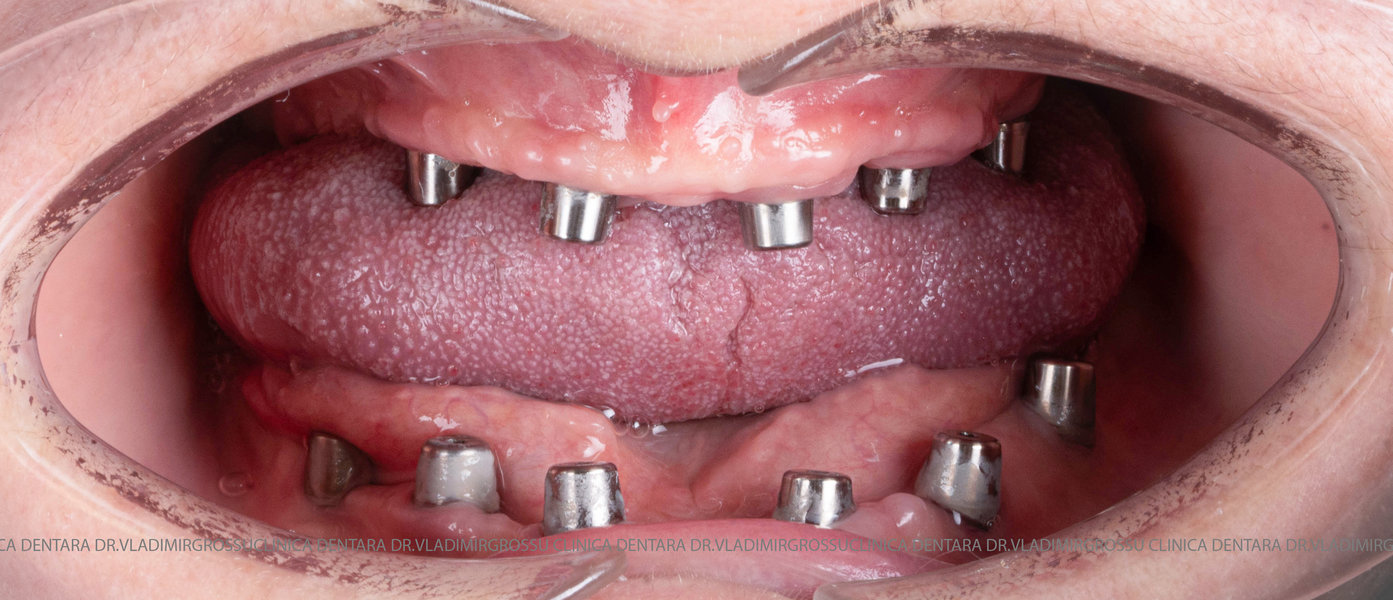

- Prima etapă constă în inserarea implanturilor și fixarea unei proteze provizorii, realizate de obicei din masă plastică frezată, ce este montată în a doua sau a treia zi postoperator. Suturile sunt îndepărtate după 5-7 zile.

- A doua etapă are loc la aproximativ 6 luni după intervenție, când se realizează proteza definitivă, care este fixată pe implanturi prin intermediul unor piese numite multiunit-uri. Această etapă presupune lucrul la nivelul multiunit-urilor, nu direct pe implanturi, reducând astfel riscul de complicații.

- Șase implanturi;

- Șase multiunit-uri, drepte sau angulate, în funcție de necesitățile protetice;

- Șase capete de confort;